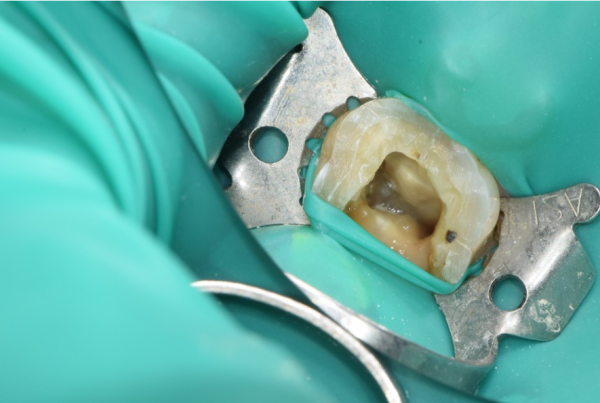

저희 태평역치과 더서울치과에서 고객님께 신경치료를 해 드리는 경우

가장 중요하게 생각하는 것은 바로 '방습환경'입니다.

충치치료를 할때 신경치료시 침, 타액, 세균이 들어가지 않도록 완벽한 환경을 만들어야 하는데요.

그때 클램프와 러버댐이라는 치과의료도구를 이용하여 진료를 하게됩니다.

이를 통해 신경치료의 좋은 예후를 기대할 수 있게됩니다.

Taepyeong Station Dental Clinic The Seoul Dental Clinic provides nerve treatment to customers

The most important thing is the moisture-proof environment.

When you treat cavities, you need to create a perfect environment to prevent saliva, saliva, and bacteria from entering during nerve treatment.

At that time, you will be treated using a dental tool called Clamp and Rubber Dam.

Through this, you can expect a good prognosis for neurotreatment.